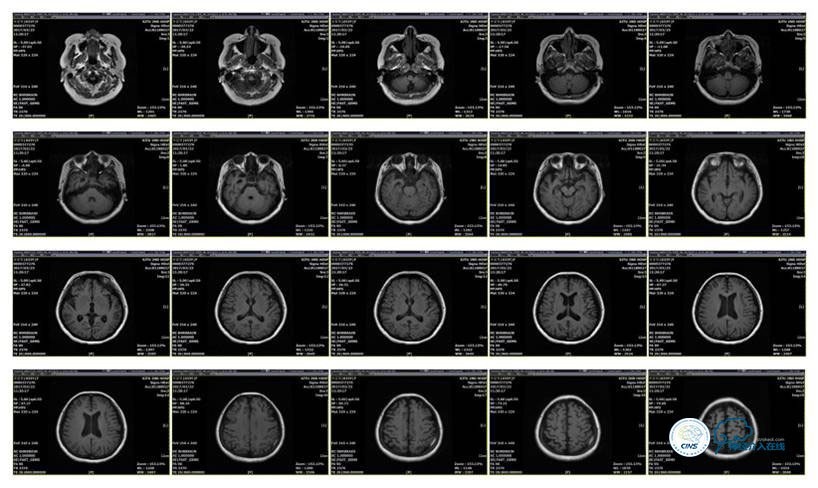

MRI T1

MRI T2

病史:患者于1年余前,因头部外伤在外院行头颅CT提示:未见异常。约3月后患者出现头痛、发作性意识丧失,在当地医院行头颅CT及MRI提示:未见明显异常。诊断为外伤性癫痫,予以对症治疗,未见明显好转。6月余前,无明显诱因出现鼻腔漏液,予以保守治疗,此后鼻腔间断漏液,漏液后头痛缓解。13天前因高热、恶心、呕吐在外院诊断为颅内感染(肺炎链球菌),予以抗炎等对症治疗2周后鼻漏停止,体温正常,CSF常规、生化正常,但头痛仍未缓解,转入我院神经内科治疗。反复腰穿颅内压450-500mmH2O左右,脑脊液常规及生化均正常。颅脑CT及MRI、MRV提示:左侧顶叶硬膜下血肿,鼻窦炎、乳突炎、左侧横窦、乙状窦闭塞、右侧横窦、乙状窦狭窄。予以华法林抗凝治疗2周,维持INR2-3,患者头痛仍无明显缓解,颅内压无降落,转入我科。

诊断:1、右侧横窦、乙状窦狭窄;2、硬膜下血肿(左侧顶);3、继发性癫痫;4、脑脊液鼻漏;5、颅内感染;6、乳突炎;7、鼻窦炎。

病理过程推理:首先是乳突炎—诱发左侧横窦乙状窦血栓最终闭塞,右侧横窦乙状窦狭窄—导致颅内高压,造成头痛及癫痫—持续颅内高压—皮层静脉回流受阻导致自发性硬膜下血肿及自发性脑脊液鼻漏—颅内感染。